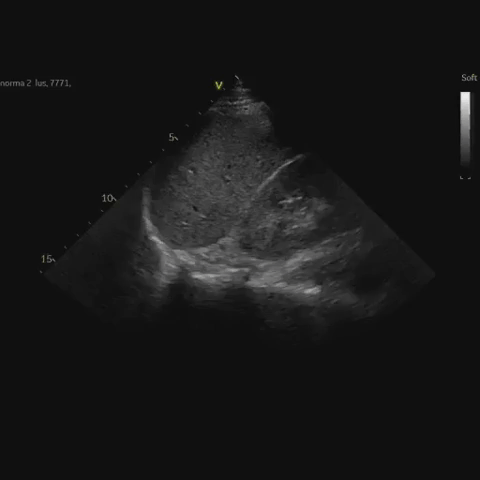

Normálny obraz pľúc v PLAPS pointe (Postero-Laterálny Anveolárny Pleurálny Syndróm). Sonda je v zadnej axilárnej čiare v oblasti kostorfrenického spojenia. Identifikujeme pohybujúcu sa bránicu, pečeň (vpravo), slezinu (vľavo). V kostofrenickom priestore je vzdušný parenchým pľúc, pre ktorý nie je viditeľný echoodraz chrbtice. V inspíriu sa „závoj“ pre ultrazvuk nepriepustných vzdušných pľúc posúva do centra obrazu.

Video s2-1 Normálny obraz z PLAPS vpravo